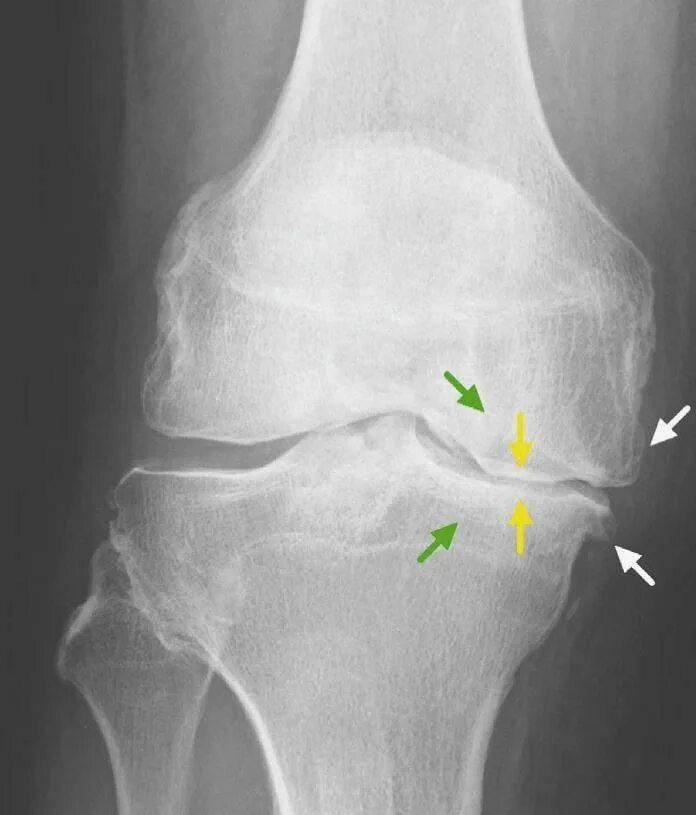

Артроз коленных суставов 2 степени инвалидность